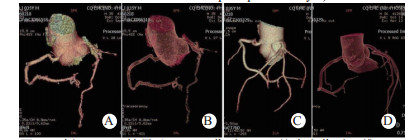

| 图 4 例6 TACS结果(A、B:伤后6 d心绞痛发作时三维CTA示冠状动脉左旋支细小,但腔内无异常密度影; C、D:半年后随访CTA示左旋支已无异常) Fig 4 Case 6 with TACS(A and B: during the attack of angina pectoris after injury 6 days, three-dimensional CTA showed small left coronary artery branch, but no abnormal density shadow in the lumen; C and D: CTA in 6-month follow-up showed no abnormalities in left lateral branch) |

心肌挫伤治疗措施包括心肌保护,限制水钠输入量和速度,适当使用激素和利尿剂,滴注高渗葡萄糖液,以促进心肌水肿吸收,改善顺应性,恢复心排。Belliister等[2]认为仅1/4~1/3的BCI需药物处理心律失常。本组资料接近该结论,用药原则是心率 > 150次/min或 > 130/min次,持续6 h以上。TACS可致心肌梗死,是应重视的特殊损伤类型,左前降支发生较多。伤后出现心绞痛即应考虑,造影证实冠状动脉裂伤、夹层、血栓形成、假性动脉瘤等,应行介入治疗,如吸除血栓安放支架。避免溶栓,尤其在合并多发伤时[6-7, 11]。缺血仅因管壁水肿或痉挛则应严密观察和相应治疗以改善心肌供血,包括使用扩血管药、激素和脱水,心绞痛则给予硝酸甘油类。本组4例患者采用非手术治愈。心脏震荡则多因胸前打击,尤其在运动员中,发生虽少但可猝死于室颤而无解剖病变[7, 12]。现场除颤可减少死亡,本组成功救治1例。